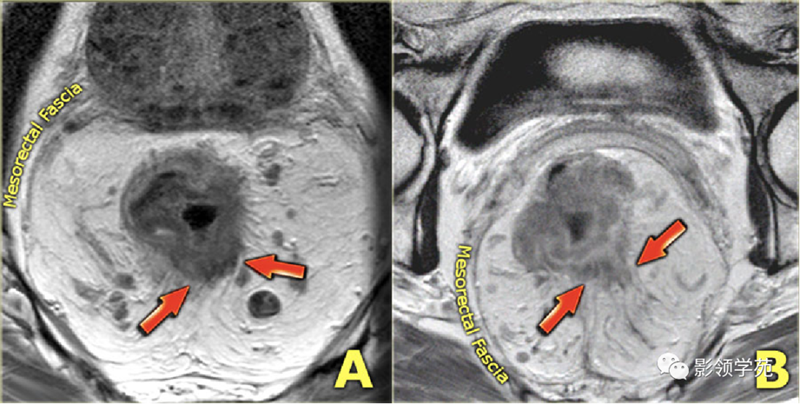

直肠癌磁共振影像

直肠癌淋巴结转移磁共振影像